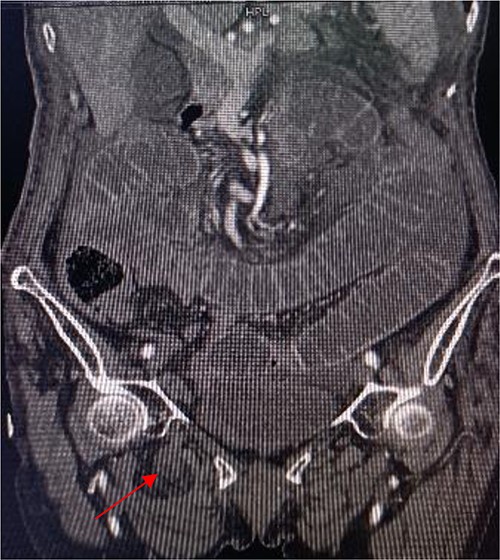

Sagittal view shows a right obturator hernia (indicated by red arrow).